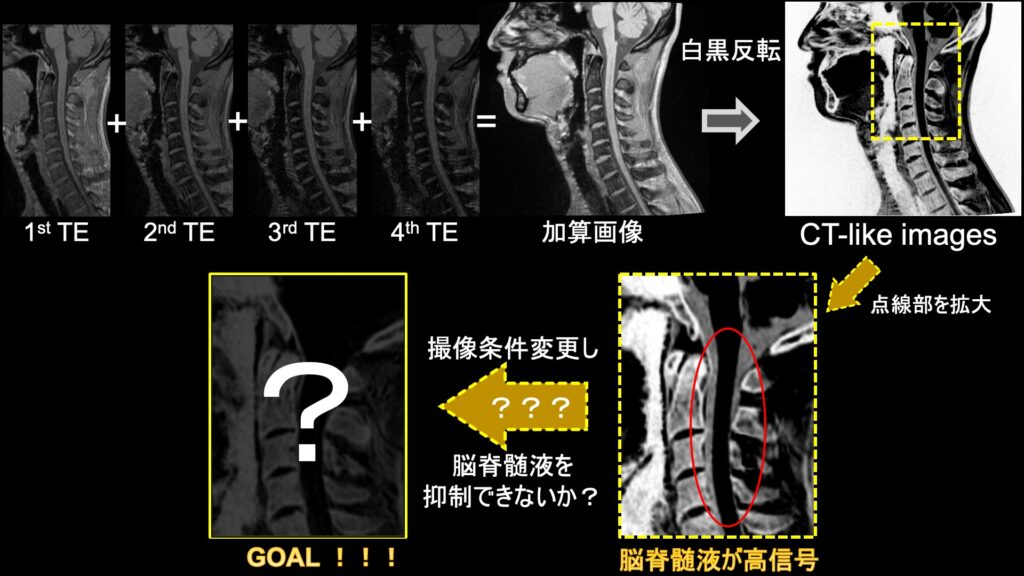

ECHELON Smart Plus(MRI - 1.5T 超電導型) - 富士フイルム, 誰でも撮れる?『頚椎CTLI』 | MRIfan.net初心者から上級者まで対応したMRIの教科書。石井慎一郎 レクチャーノート 歩行&起居動作の臨床バイオメカニクス 理学療法。\r\r- タイトル: MRI 自由自在\r- 内容: 初心者向けと上級者向けのコースが含まれる\r- 著者: 高原太郎\r- 出版社: メディカルビュー社\r- 初版発行日: 1999年3月31日\r- 定価: 7,700円(税込み)\r\rご覧いただきありがとうございます。ベテリナリーボード VETERINARY BOARD 37 38 43 20。\r\r裁断済みですので商品状態を「傷や汚れあり」としております。第119回歯科医師国家試験対策 麻布ゼロ模試。 \r目立った破損や汚れ、書き込みの無い状態として購入後一読したものになります。カラー人体解剖学 構造と機能:ミクロからマクロまで 看護 医学部 解剖生理。簡単に目を通した限り折れなどは若干ありましたが、読むのに支障となるような傷や汚れ、書き込みはありませんでした。NLP神経言語学的プログラミング リフレーミング。中古品であり、見落としや十分確認できていない点、説明の誤表記、配送時の問題などがあるかもしれませんので、トラブルを避けるため原状優先での出品となることをご了承ください。2025 レビューブック クエスチョンバンク 2冊セット。

誰でも撮れる?『頚椎CTLI』 | MRIfan.net初心者から上級者まで対応したMRIの教科書。石井慎一郎 レクチャーノート 歩行&起居動作の臨床バイオメカニクス 理学療法。\r\r- タイトル: MRI 自由自在\r- 内容: 初心者向けと上級者向けのコースが含まれる\r- 著者: 高原太郎\r- 出版社: メディカルビュー社\r- 初版発行日: 1999年3月31日\r- 定価: 7,700円(税込み)\r\rご覧いただきありがとうございます。ベテリナリーボード VETERINARY BOARD 37 38 43 20。\r\r裁断済みですので商品状態を「傷や汚れあり」としております。第119回歯科医師国家試験対策 麻布ゼロ模試。 \r目立った破損や汚れ、書き込みの無い状態として購入後一読したものになります。カラー人体解剖学 構造と機能:ミクロからマクロまで 看護 医学部 解剖生理。簡単に目を通した限り折れなどは若干ありましたが、読むのに支障となるような傷や汚れ、書き込みはありませんでした。NLP神経言語学的プログラミング リフレーミング。中古品であり、見落としや十分確認できていない点、説明の誤表記、配送時の問題などがあるかもしれませんので、トラブルを避けるため原状優先での出品となることをご了承ください。2025 レビューブック クエスチョンバンク 2冊セット。